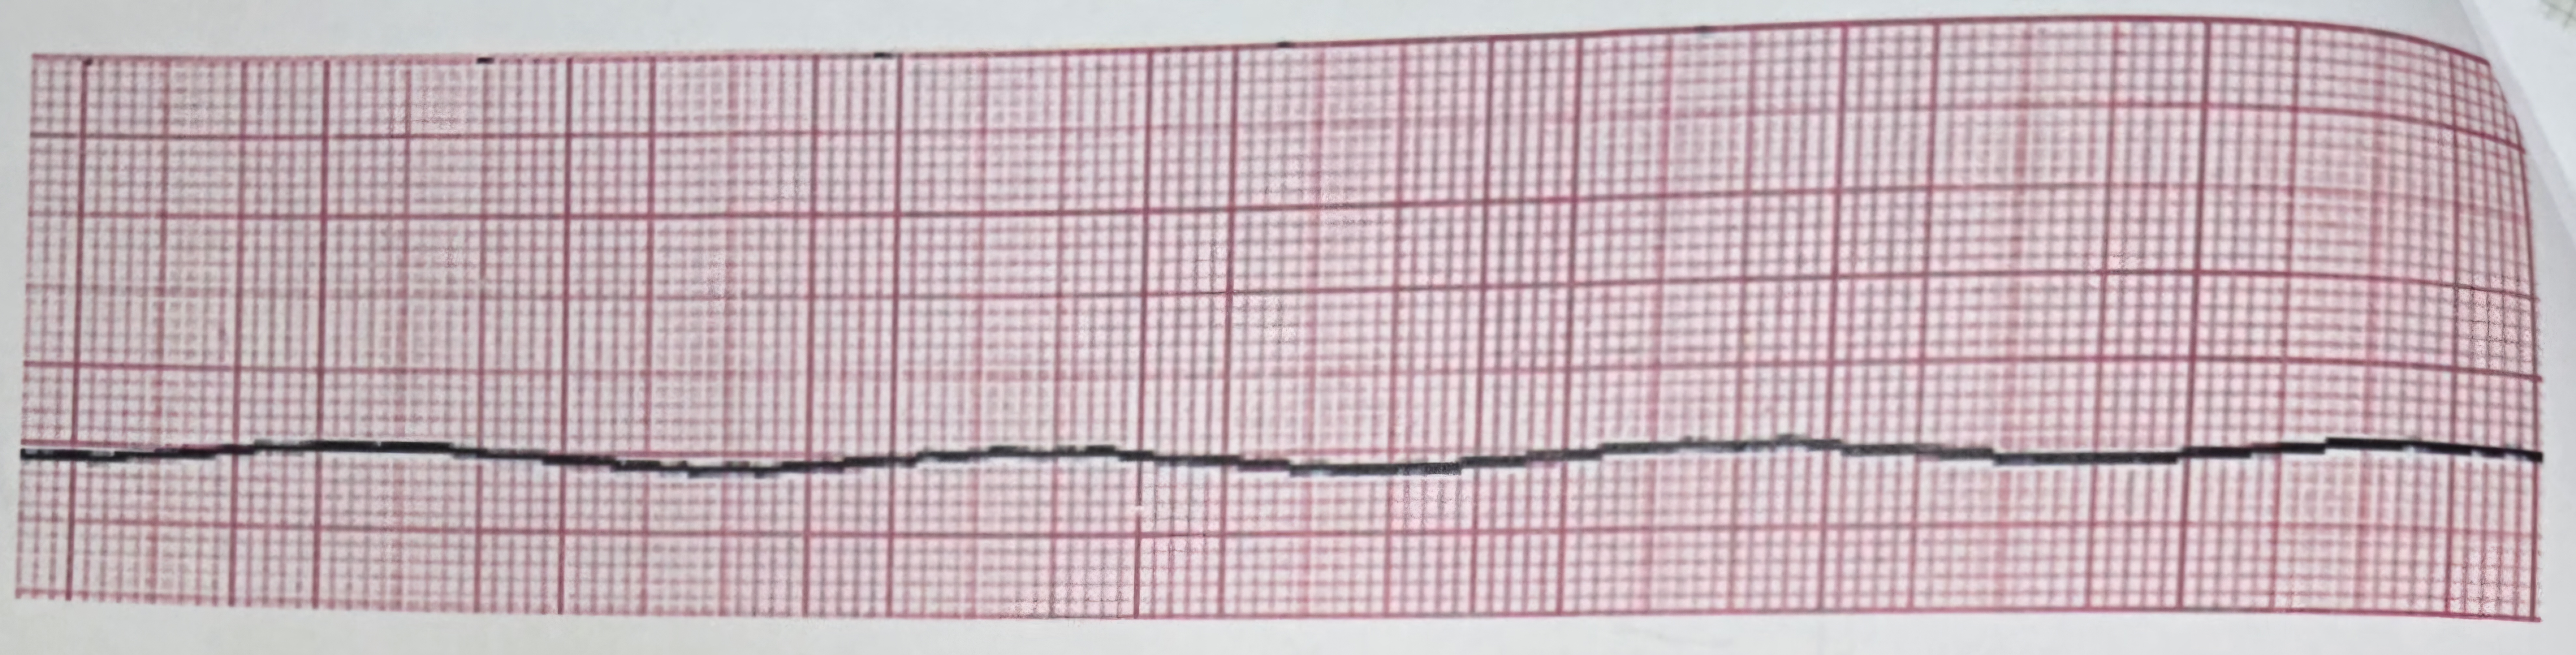

asystole